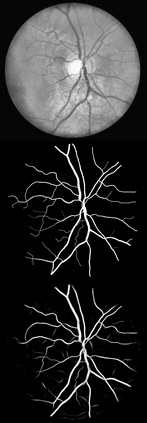

U-Net has been providing state-of-the-art performance in many medical image segmentation problems. Many modifications have been proposed for U-Net, such as attention U-Net, recurrent residual convolutional U-Net (R2-UNet), and U-Net with residual blocks or blocks with dense connections. However, all these modifications have an encoder-decoder structure with skip connections, and the number of paths for information flow is limited. We propose LadderNet in this paper, which can be viewed as a chain of multiple U-Nets. Instead of only one pair of encoder branch and decoder branch in U-Net, a LadderNet has multiple pairs of encoder-decoder branches, and has skip connections between every pair of adjacent decoder and decoder branches in each level. Inspired by the success of ResNet and R2-UNet, we use modified residual blocks where two convolutional layers in one block share the same weights. A LadderNet has more paths for information flow because of skip connections and residual blocks, and can be viewed as an ensemble of Fully Convolutional Networks (FCN). The equivalence to an ensemble of FCNs improves segmentation accuracy, while the shared weights within each residual block reduce parameter number. Semantic segmentation is essential for retinal disease detection. We tested LadderNet on two benchmark datasets for blood vessel segmentation in retinal images, and achieved superior performance over methods in the literature. The implementation is provided \url{https://github.com/juntang-zhuang/LadderNet}